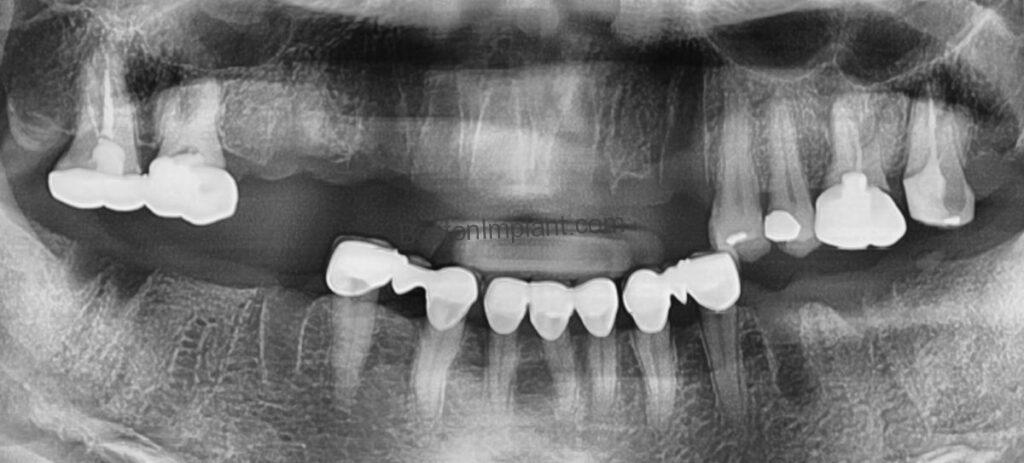

A remarkable 51-year-old woman arrived at my practice in Boston, a beacon of hope sought after enduring a truly harrowing ordeal. Imagine: fourteen teeth extractions, a significant portion of her smile and ability to face the world, had been wrested away at a distant clinic, a full two hours from the sanctuary of my office. Now, she navigated her days relying on a flimsy flipper denture for her upper arch, a constant, unwelcome reminder of her loss. This temporary fix, meant to offer a semblance of normalcy, instead delivered only discomfort and robbed her of the natural beauty she yearned to reclaim. The unspoken plea in her eyes was palpable – a desperate longing for a permanent, unwavering smile that would finally restore her confidence. In that initial, delicate encounter, a profound respect for her vulnerability prevented me from capturing any photographs; the story etched in her expression was powerful enough.

To thoroughly understand her bone structure, we began with a CBCT (Cone Beam Computed Tomography) scan, a sophisticated 3D X-ray providing a detailed blueprint of her jaw. Following a comprehensive consultation and the development of a tailored treatment plan, we decided on the placement of 12 dental implants. For optimal aesthetics in the upper front, we planned for tooth-colored abutments, while utilizing titanium abutments on the molars for enhanced durability. (You can learn more about these components in our blog post, ‘Custom Abutments of Dental Implants‘.) While our initial aim was to replace each missing molar with an implant, we strategically chose to forgo implants in two specific non-stress-bearing areas of the upper front, which also offered a more affordable option for the patient.